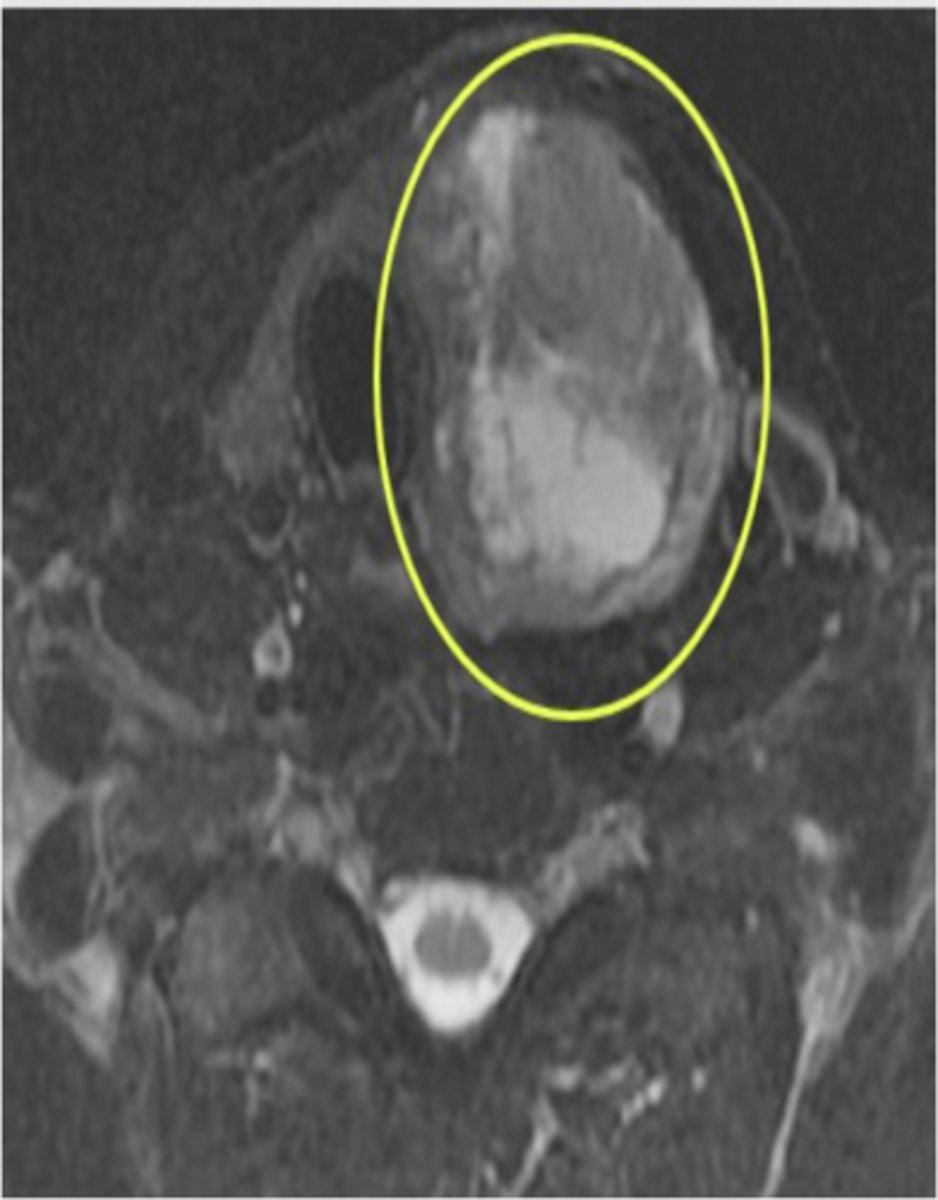

What is pericardial effusion?

Excess fluid in the pericardial space.

What causes pericardial effusion?

Infectious and noninfectious processes.

How much fluid is normally present in the pericardial sac?

Approximately 30-50 mL.

What are the symptoms of pericardial effusion?

Dyspnea, reduced exercise tolerance, impaired cardiac output, and death in severe cases.